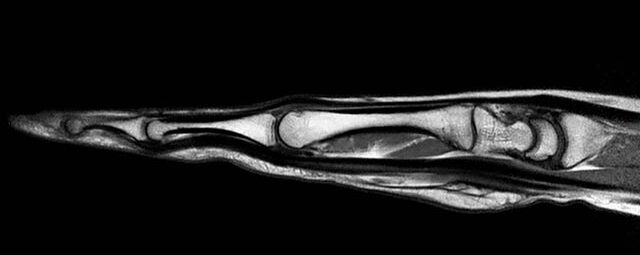

Gelenke

Hand

• Beurteilung von Knochen, Bändern und anderen Weichteilstrukturen der Gelenke nach Unfall.

• Arthrosediagnostik (Knorpelschaden)

• Impingement-Symptomatik

• Ursachenklärung bei wiederholter spontaner Gelenkluxation

• Ausbreitungsdiagnostik bei Gelenkentzündung, z.B. im Rahmen von rheumatischen Grunderkrankungen

Arthrographie

• MR-Arthrographie – nach örtlicher Betäubung und gründlicher Desinfektion der Haut wird unter Lagekontrolle mit Röntgen-Durchleuchtung eine kleine Nadel in den Gelenkraum positoniert und darüber ein MR-taugliches Kontrastmittel in den Gelenkraum gespritzt. Danach wird die Nadel entfernt. Anschließend erfolgt die MRT des Gelenkes. Diese Methode stellt kleine anatomische Strukturen des Gelenkraumes verbessert dar, z.B. zur Therapieplanung vor Arthroskopie bei Sportverletzungen der Schulter oder Gelenkinstabilität.